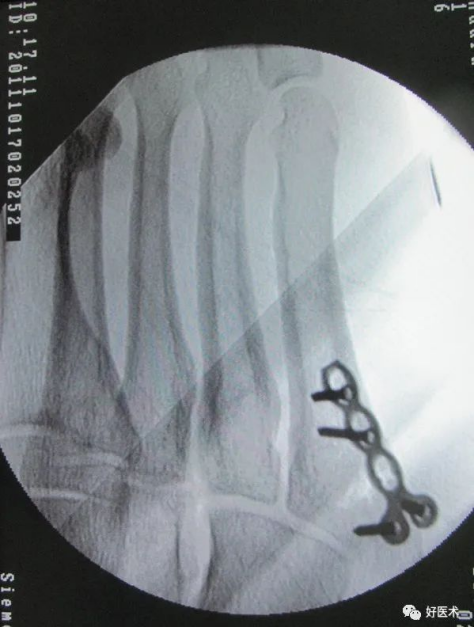

微型钩钢板固定——一种新的有效手术方法适用于第五跖骨基底部I区和II区骨折(移位﹥2毫米)或者伴有小的粉碎型撕脱骨折块。

第五跖骨基底骨折应用钩钢板固定法治疗更为牢固可靠,且应力性能好;对于粉碎骨折、移位较明显的骨折,钩钢板法尤其具有明显优势,钩钢板的尖头钩可牢固抓持粉碎骨块,实现可靠复位,能更有效缩短患者住院时间、促进骨折愈合、恢复患足功能、促进早期功能锻炼,疗效显著且安全性高,是治疗第五跖骨基底骨折的一种安全有效的方案。

设计:微型管状的钩板的最后一个孔被设计成可充当用于压缩作用的钩,抓粉碎骨折块,防止移位,并且在基底部可以控制旋转稳定。